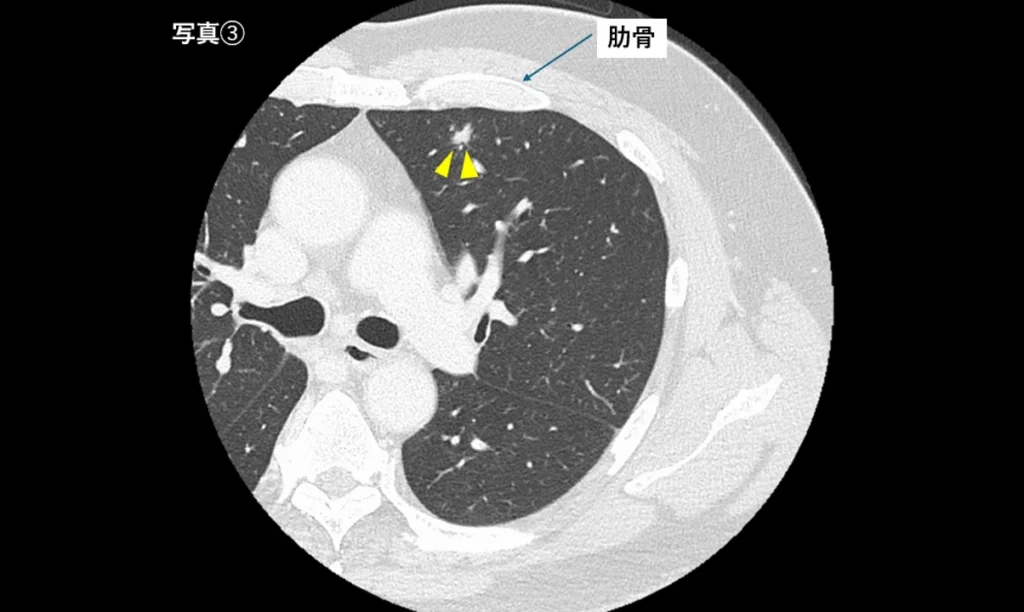

肋骨の裏側にある腫瘍(写真③)

肋骨と重なる位置の病変は、レントゲンでは判別が難しいことがあります。